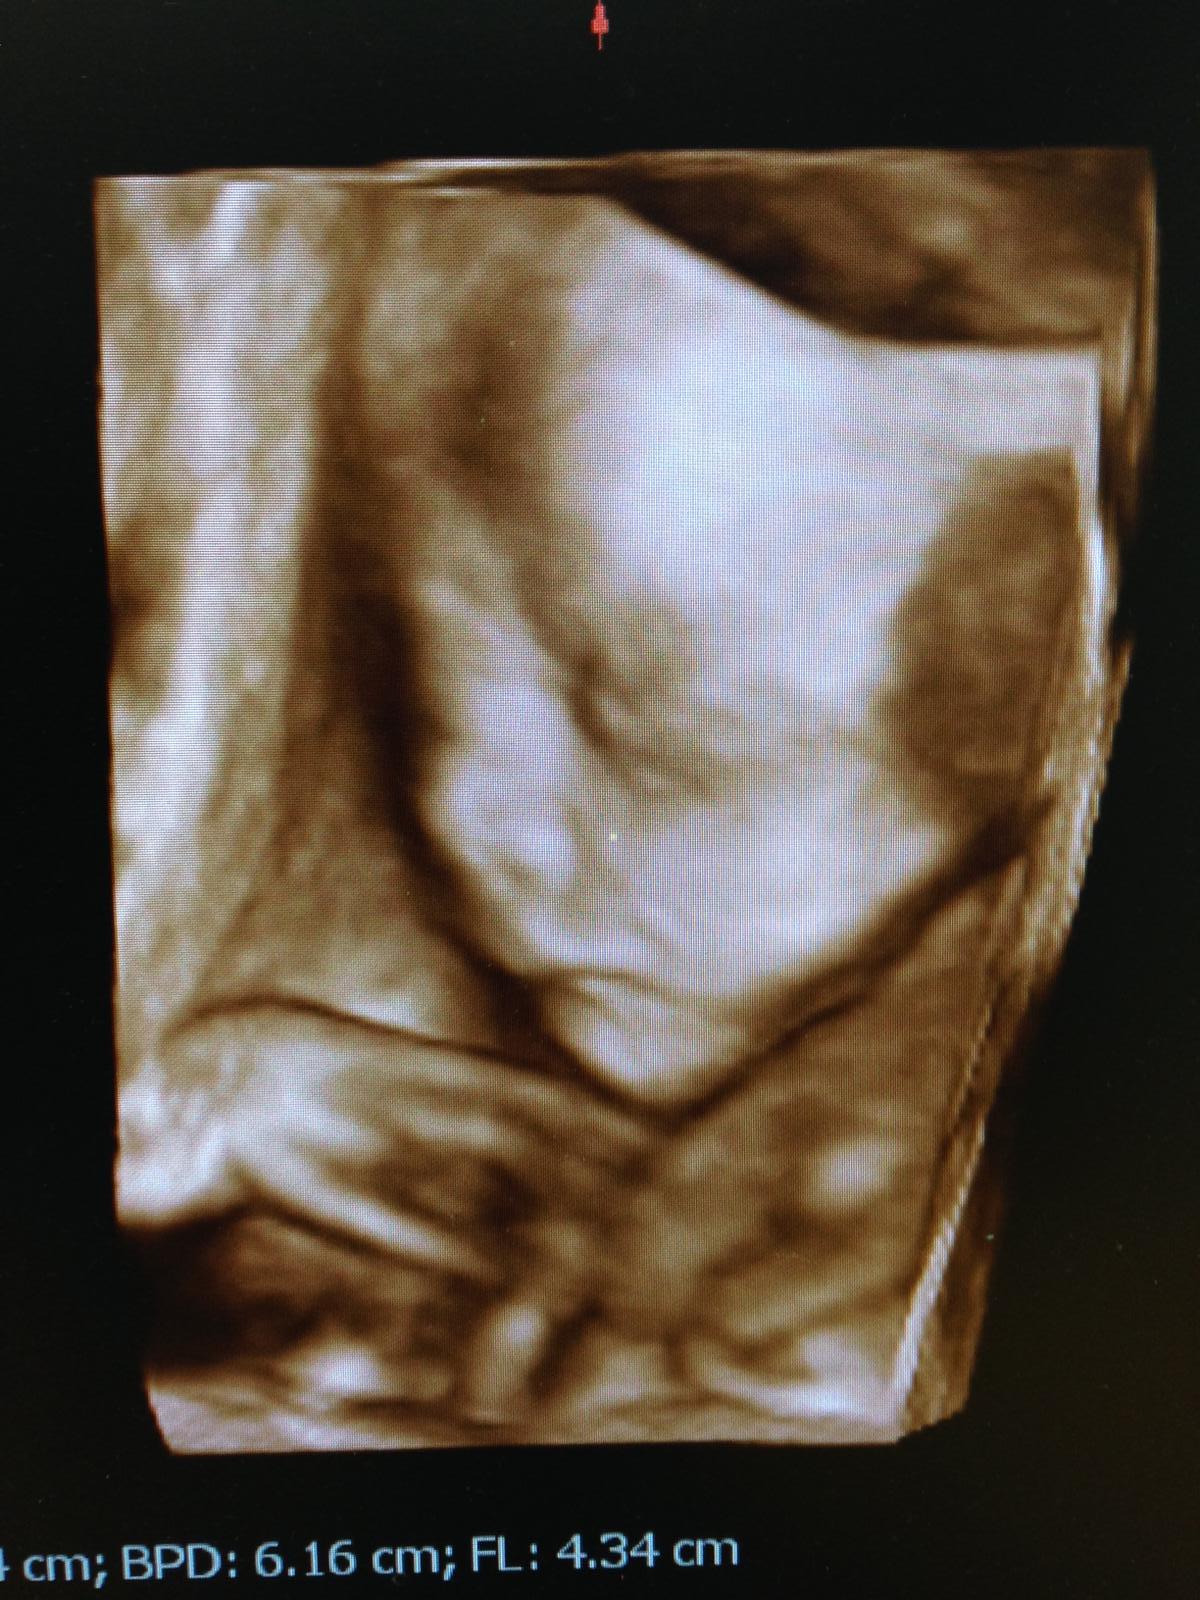

náš malý krpčok v 26tt